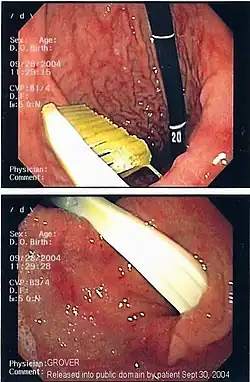

| A foreign body - in this case a swallowed toothbrush - located in the stomach cavity by using an endoscope. | |